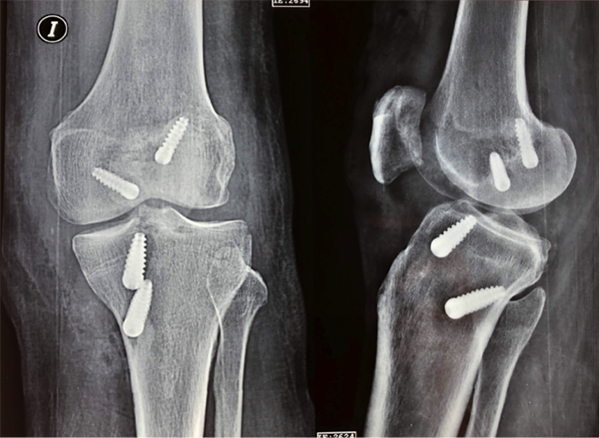

Se respetaron los tendones de la pata de ganso para la reconstrucción ligamentaria medial. Completamos según técnica la realización de túneles tibial y femoral anatómicos monobanda del LCP. La reconstrucción del LCA se realizó mediante una técnica transtibial modificada (TTM). Se fijaron ambas plásticas con tornillos de interferencia de titanio (South American Implant) (figs. 7 y 8).

Figura 8: Rx frente y perfil: Resultado luego de la reconstrucción anatómica de LCA y LCP. Rx perfil: detalle de huella de toma de taco óseo sobre polo superior de rotula de la toma del injerto DTC.